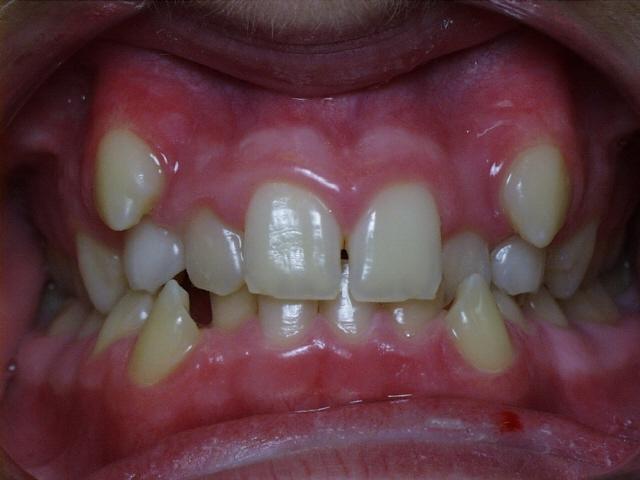

Moderate crowding with crossbites of the front teeth.  Treatment time was 24 months.  No permanent teeth were extracted in this case, but two deciduous cuspids seen in the initial photo were extracted after the braces were placed.  The molars were class 3 (lower molars too far forward at the start of treatment).

Before  lmao1.jpg (29692 bytes)     lmao3.jpg (25621 bytes)  After